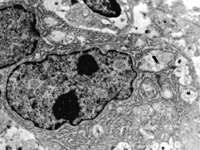

5-2-1 傷后第1天,表皮凝固性壞死,真皮淺層膠原纖維變性  HE×100